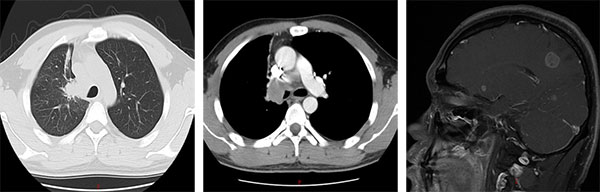

2016年5月,31岁的小申连续多日出现咳嗽、痰中带血症状,左侧后背还时常隐痛。起初他以为是熬夜工作劳累所致,直到症状持续加重,才在家人催促下前往当地医院就诊。胸部CT显示左肺上叶存在占位性病变,进一步检查后发现,癌灶已转移至右肺及纵隔淋巴结,头部MRI更提示脑部存在多发转移灶;支气管镜活检最终确诊为肺腺癌。“拿到病理报告,被医生告知所患疾病是晚期肺癌(Ⅳ期)伴脑转移的那天,我在医院走廊里坐了很久,反复问自己:为什么是我?”无烟酒习惯、无家族肿瘤病史的小申在医院走廊枯坐良久,始终无法接受自己已是晚期癌症的事实。

“刚开始服药时,心里总有些忐忑,怕效果不如预期。”服药第3天,咳嗽症状明显减轻;8周后复查,胸部CT显示肺部病灶显著缩小,阻塞支气管的肿瘤组织基本消失;70天,头颅核磁也提示脑转移灶体积缩小、部分微小病灶完全消失。小申的抗癌小本本上记录着他每一天的状况改善。就这样,在治疗的第三个月,小申就重新回到了工作岗位,气色越来越好,变得和常人无异。

治疗前(2016年12月)

治疗后(2025年06月)